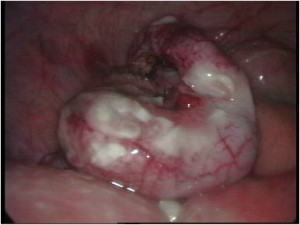

Acute Scrotum (Right scrotal Abscess)

Torsion of Left Undescended Testis (Pre operative and Operative Photo)